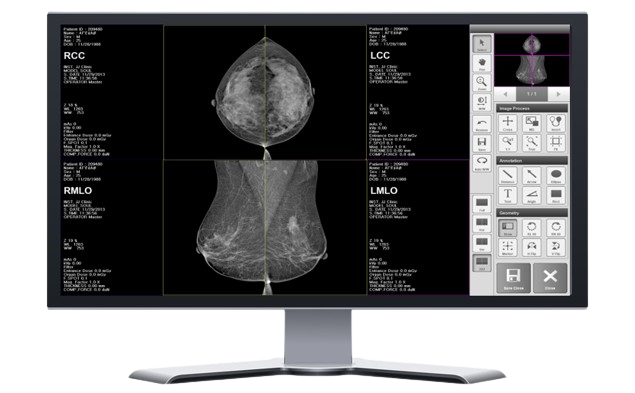

IMAGE ACQUISITION SOFTWARE “BRESTATION LITE”

By applying intuitively designed buttons and various measurement tools, the user can conveniently obtain and check the patient's image and control the system with the touch screen to improve user convenience.